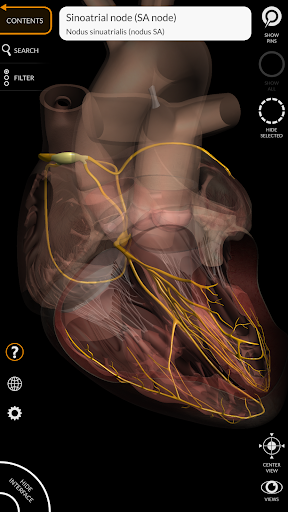

"Anatomy 3D Atlas" vous permet d'étudier l'anatomie humaine de manière simple et interactive.

Grâce à une interface simple et intuitive, il est possible d'observer chaque structure anatomique sous n'importe quel angle.

Les modèles anatomiques 3D sont particulièrement détaillés et avec des textures jusqu'à une résolution de 4k.

La subdivision par régions et les vues prédéfinies facilitent l'observation et l'étude de parties individuelles ou de groupes de systèmes et les relations entre différents organes.

MODÈLES ANATOMIQUES 3D

• Système cardiovasculaire

• Système nerveux

• Fonction de transparence